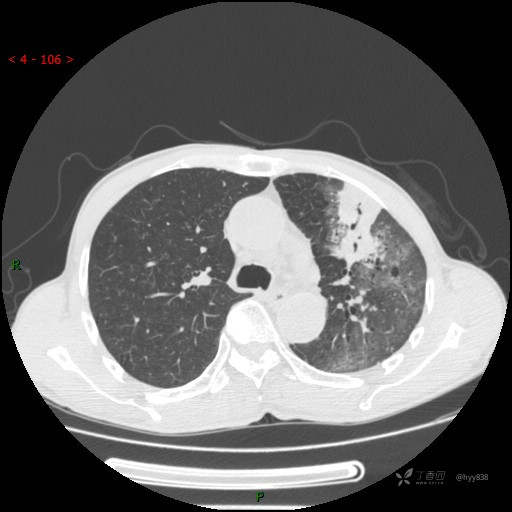

胸部CT平扫(首次)